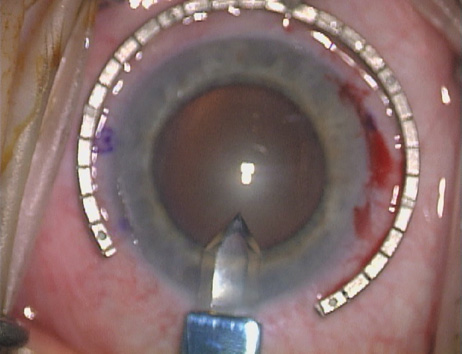

Case 3 is a 48-year-old bilateral hyperope who presented for a refractive surgical consultation. The refraction in his left eye was found to be +3.25 +1.75 × 85. Keratometry was somewhat flat but confirmed WTR cylinder as did corneal topography. Based upon the patient's age, refraction, and somewhat shallow anterior chambers, the decision was made to proceed with a refractive lens exchange. The NAPA nomogram called for LRIs of 55 to 60 degrees with intraoperative pachymetry. Intraoperative keratoscopy confirmed the steep 85-degree meridian (Figs. 2029).

Fig. 20. Keratoscopy, after lifting of the speculum to relieve induced pressure and distortion of the corneal mires, confirms the steep axis of 85 degrees.

Fig. 21. The broad hash marks of the fixation ring are centered just off of the 6:00 limbal orientation mark, over the 85 degree meridian in this left eye. The two cut RK marker is positioned at one extent of the LRI, just under 30 degrees from the central steep meridian and the cornea is marked.

Fig. 22. A second mark is made delineating the opposite extent for a total arc length of just under 60 degrees.

Fig. 23. Following pachymetry measurement over the entire arc length of the incision, an adjustable micrometer diamond knife is set to 90% of the thinnest reading obtained.

Fig. 24. The inferior incision is begun.

Fig. 25. The incision is completed for a total arc length of just under 60 degrees.

Fig. 26. The opposing superior LRI is begun.

Fig. 27. The incision is completed at the corneal mark.

Fig. 28. 6A side-port incision is created for the surgeon's non-dominant right hand, taking care not to intersect the LRI.

Fig. 29. The single-plane RLE incision is completed.